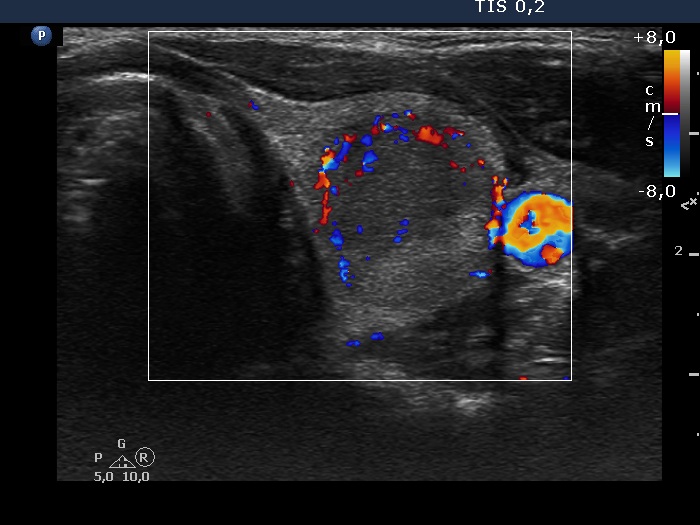

Right lobe, longitudinal scan

Left lobe, another transverse scan, color Doppler mode. The lesion shows perinodular vascularization.